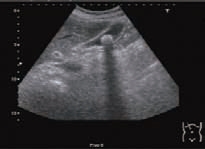

1)胆囊腔内高/强回声团。胆囊结石与周围液性胆汁声阻抗差较大,使得胆囊结石的边界可清楚显现。由于结石本身的形状、结构和成分不同,其回声形态可有较大差别。结构较致密且表面较光滑的结石,表现为新月形强回声(图5-6);结构较松散的结石,由于透声性好,结石的全貌均可被显示,呈满月形强回声(图5-7);数个堆积在一起的小结石可产生堆积状、沙堆状强回声(图5-8)。

图5-8 胆囊多发结石(堆积状、沙堆状)及声影